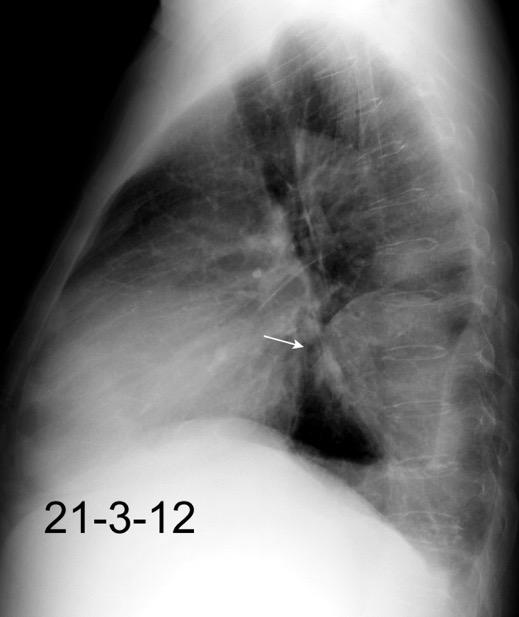

Líneas paraespinales formando un “paréntesis” por encima del diafragma. El signo señala el origen “intratorácico” de la lesión.

Conrad A et al. Pott’s disease associated with large and multiple abscesses in a 30-year-old migrant from Chad. BMJ Case Rep 2018

(lesiones toracoabdominales) La divergencia de las líneas paraespinales apunta a lesión toracoabdominal, que desde el tórax desciende y penetra en el abdomen.

Signo del “iceberg” positivo en Tb vertebral

Afectación por vía hematógena. Región dorsolumbar más frecuente. Afectación inicial: irregularidad de los platillos vertebrales, disminución del disco intervertebral con esclerosis ósea adyacente. Kim. Radiographics.2001